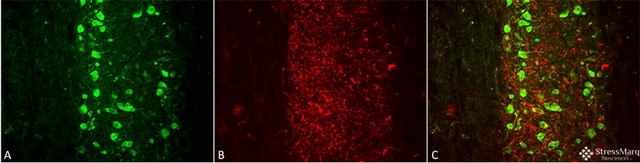

IHC, IP, WB

immunohistochemistry: suitable, immunoprecipitation (IP): suitable, western blot: suitable

Fusion protein amino acids 1-708 (full length) of rat MMP9

Detecs ~92kDa and ~82kDa (pro and active forms)